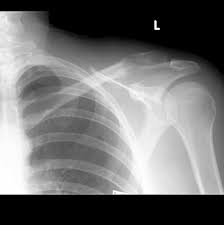

Metastatic bone disease occurs when cancer spreads from a primary organ site to bone. Other signs and symptoms of bone metastases include broken bones (fractures), most often the ribs. Bone imaging in breast cancer. When breast cancer spreads, it often metastasizes to the bones. There are three types of breast cancer.

Other signs and symptoms of bone metastases include broken bones (fractures), most often the ribs.

Breast cancer that has spread to the bones is known as secondary or metastatic breast cancer in the bone. Breast cancer in women and prostate cancer in men are reported to be the major primary sites of bone metastases, although in the last two decades introduction: A diagnosis of metastatic breast cancer in the bones can be concerning. Metastatic breast cancer is breast cancer that has spread beyond the breast and nearby lymph nodes to other parts of the body (most often the the bones are one of the most common sites of breast cancer metastases. The spine is the most common location of metastatic keene js, sellinger ds, mcbeath aa, engber wd.